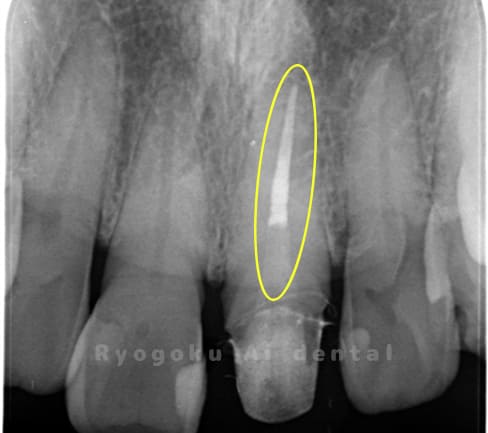

Case11

-

- 原因

- 慢性根尖性歯周炎

- 治療内容

- マイクロエンド

- 治療費用

- 77,000円(被せ物は含まない)

前歯が痛いとのことでご来院された患者様です。マイクロスコープ、MTAを用いて、緊密に根管充填を行い、現在、痛みもなく経過は良好です。

<リスク・副作用>

術後は痛み、腫れ、痺れなどの副作用が生じる場合があります。症状が再発する可能性があります。